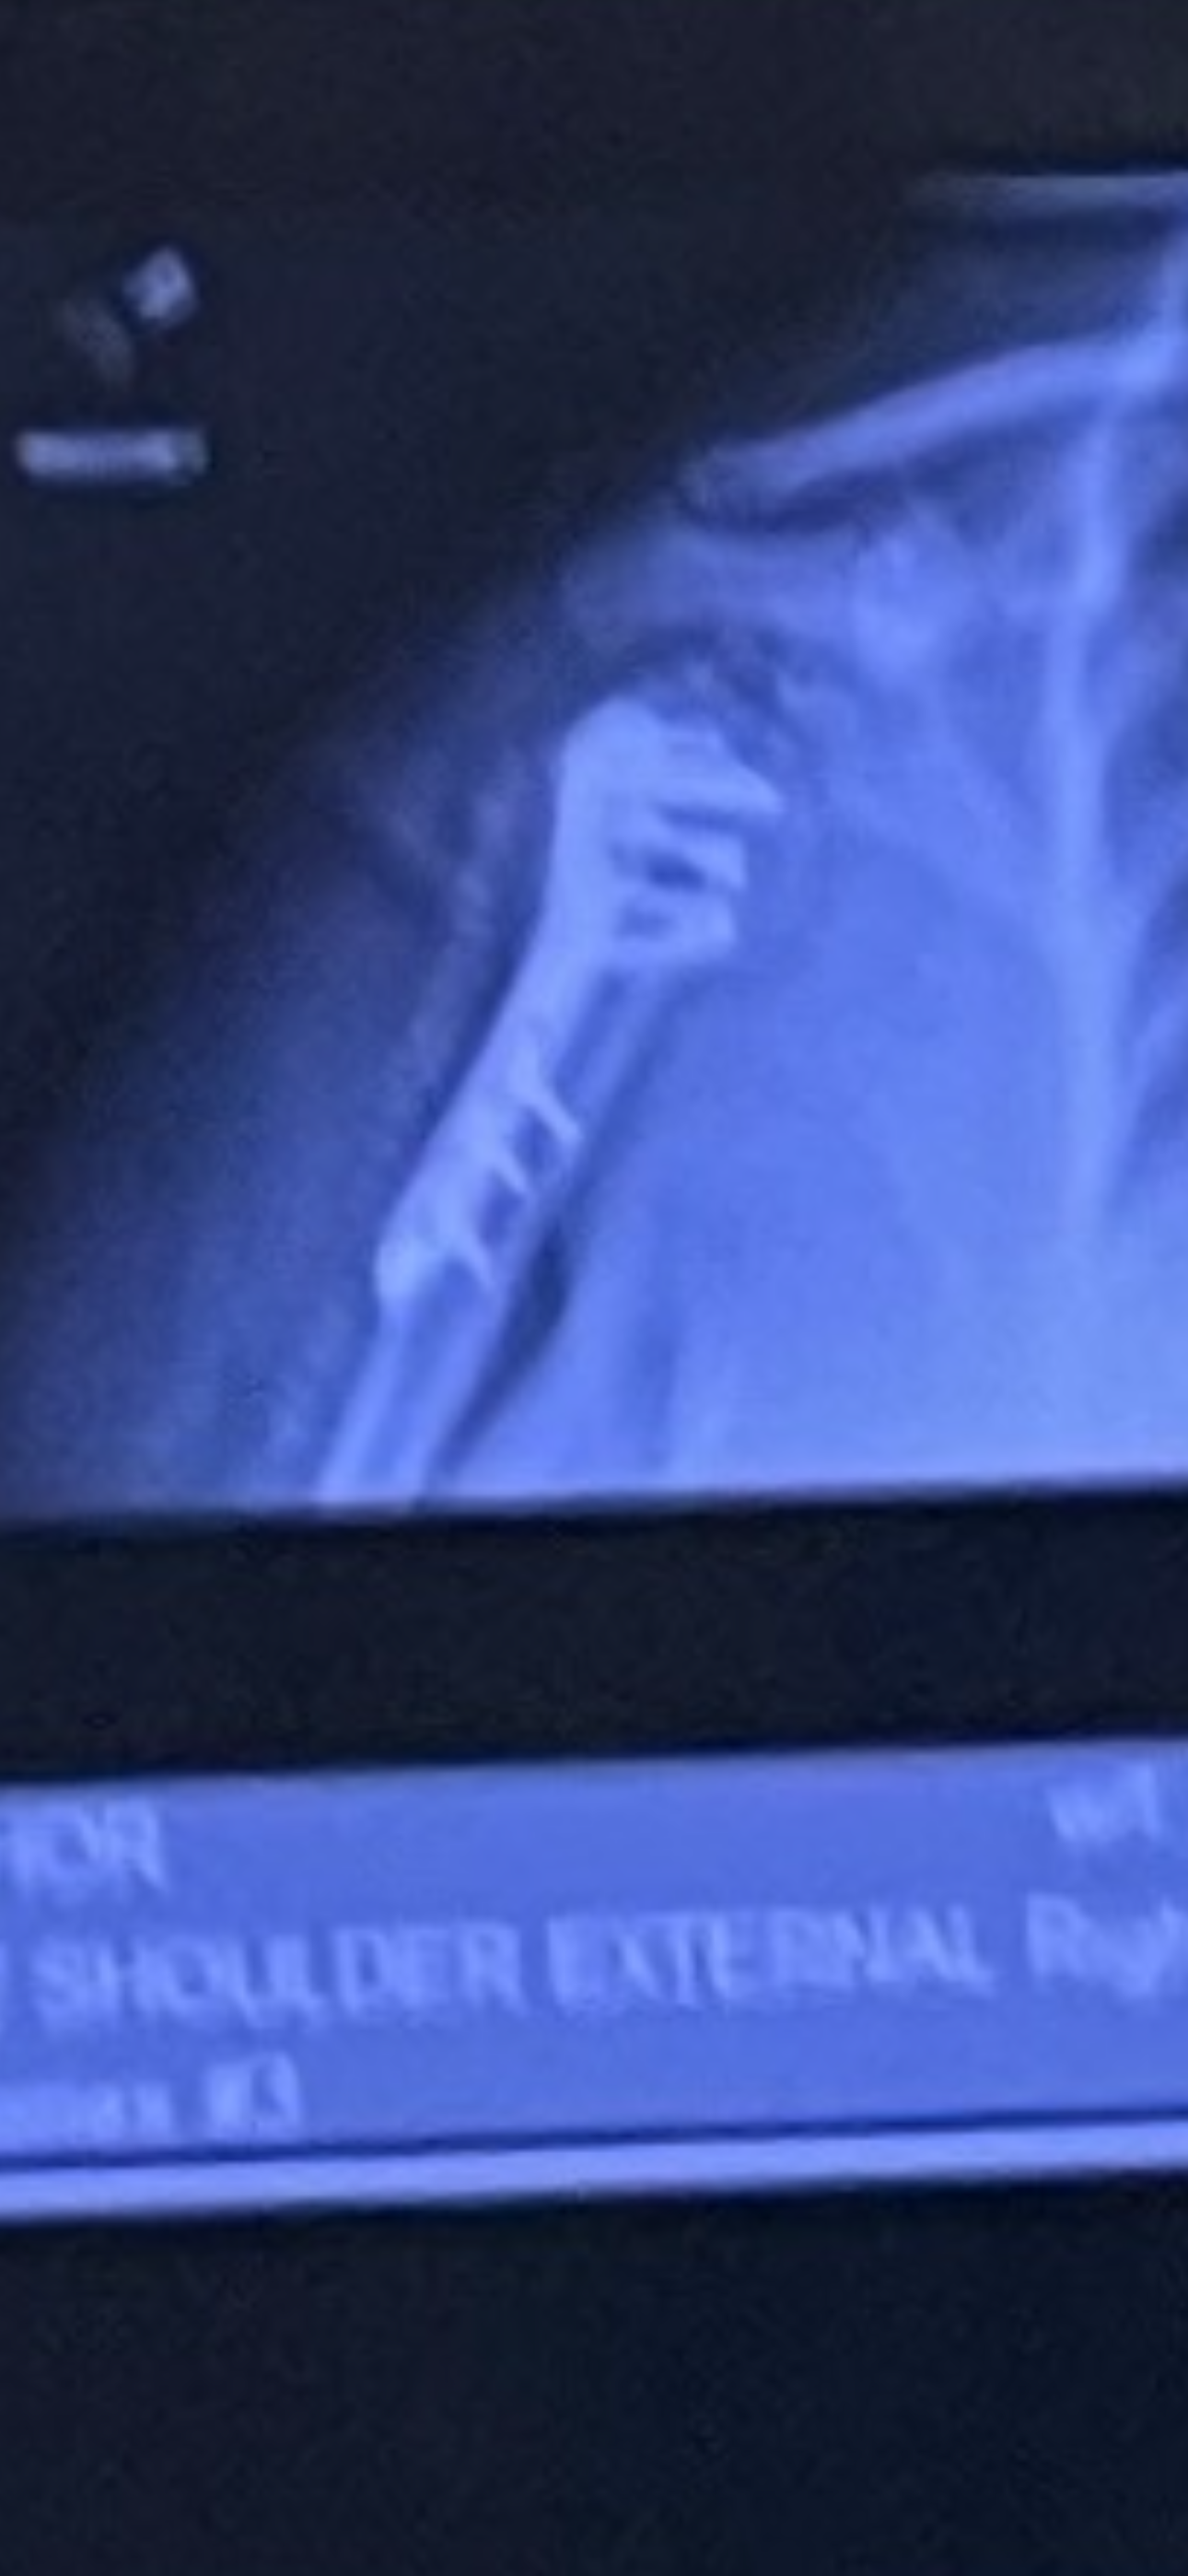

Many of you know that I was in a pretty serious motorcycle accident in February this year, which required emergency surgery on my arm, and I'm still waiting to get approval for a knee replacement. UCI Hospital just wrapped up their billing, and I am left with a crushing copay of $24,363.98!!! I am reaching out to my friends and family for help. This is completely devastating. People with insurance should not be left with this kind of life-crushing debt if they are in an accident. I was initially taken to UCI Trauma Center because it was the closest, and my situation was critical. I had Kaiser insurance, but because Kaiser was too overcrowded, they had me remain at UCI for the surgery and recovery, but they processed the claim as out of network. I didn't have a choice!! I was broken and helpless!!